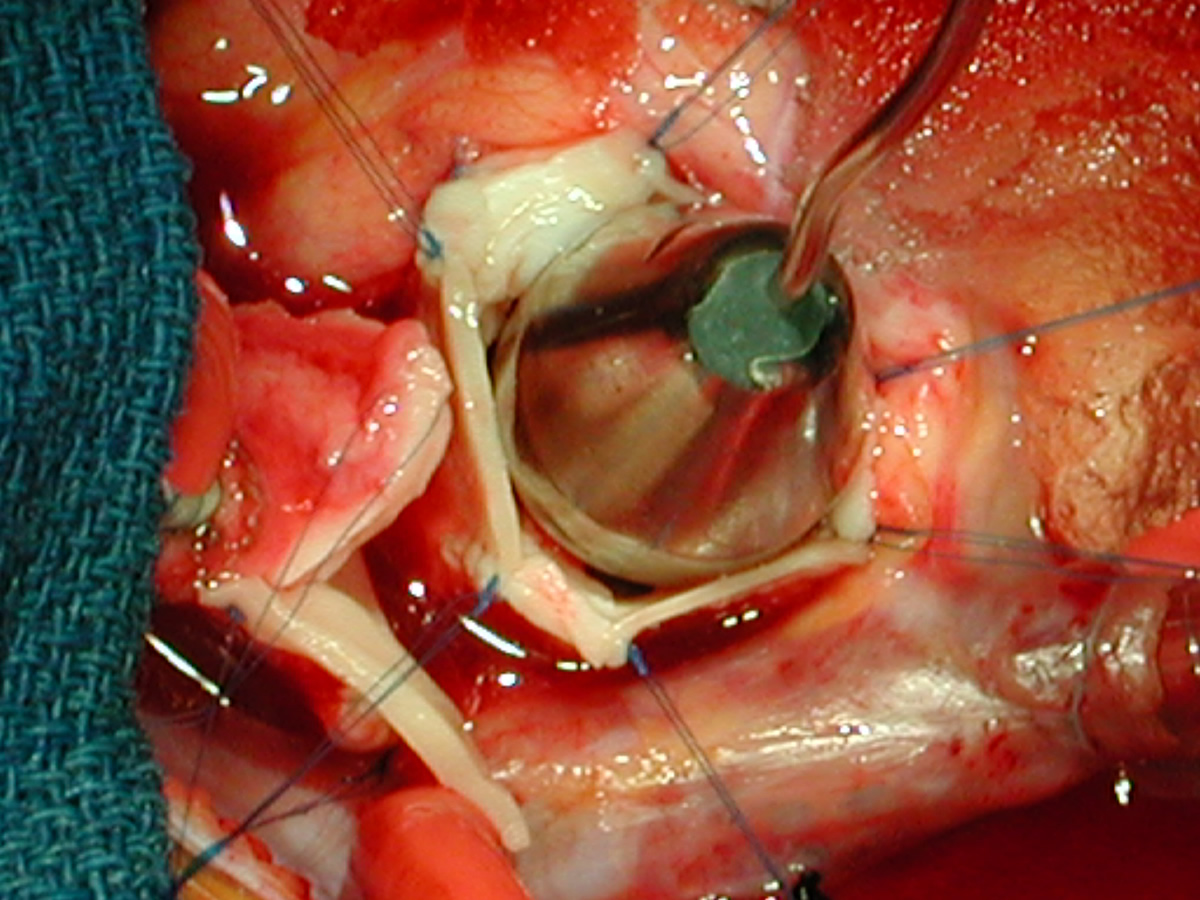

Indications for surgery include symptoms of diminished exercise tolerance, syncope, or angina. Other indications would include 1) systolic ascending aorta gradient greater than 50 mm Hg, 2) aortic valve insufficiency, or 3) evidence of compromised coronary artery perfusion. These patients should undergo surgery at a relatively early age because of the detrimental effect of the high proximal aortic pressure on the coronary arteries with the possibility for accelerated atherosclerotic changes. These patients typically have a thickening of the aortic wall at the sinotubular junction. This abnormal thickening may extend into the ascending aorta and even into the aortic arch. In some patients, this abnormal thickening creates stenosis of the coronary ostium.

The surgical history of operations for supravalvar aortic stenosis is shown in Table 1. Dwight McGoon and John Kirklin [2] from the Mayo Clinic first reported a one-patch teardrop-type repair of supravalvar aortic stenosis in 1961. Donald Doty [3] reported the use of an inverted Y-shaped patch which extended into two of the aortic valve sinuses in 1977. The technique described in this monograph is that of A. Gerard Brom, [4] with three patches placed into the three aortic valve sinuses. This frequently also requires a patch in the distal ascending aorta. Most recently, John Myers [5] described an approach with three incisions into the three coronary sinuses and corresponding counterincisions into the distal ascending aorta which then insert into the openings created in the proximal ascending aorta. This technique has the advantage of not requiring autologous patch material, but is technically more demanding.

The operative approach is through a median sternotomy with the use of cardiopulmonary bypass and bicaval venous cannulation. The first dose of cold blood cardioplegia is antegrade; the remaining doses are retrograde.

High ascending aortic cannulation adjacent to the innominate artery for maximum exposure of the ascending aorta and to allow length for positioning of the patch in the ascending aorta.

Pulmonary homograft or pericardial patches (tanned in glutaraldehyde) for the “shields”. These patches should not be too large – this will lead to aortic insufficiency.

First coronary sinus incision in noncoronary sinus to facilitate exposure of the incisions into the coronary orifice sinuses.

In most cases, the right coronary artery sinus should be opened to the left of the coronary orifice and the left coronary artery sinus to the right of the coronary orifice. Occasionally one may not have enough room between a coronary orifice and the aortic valve; in this case the incision site should be tailored to the situation.

Ensure similar orifice sizes between the proximal and distal ascending aorta after patch augmentation by the use of a sizing dilator.